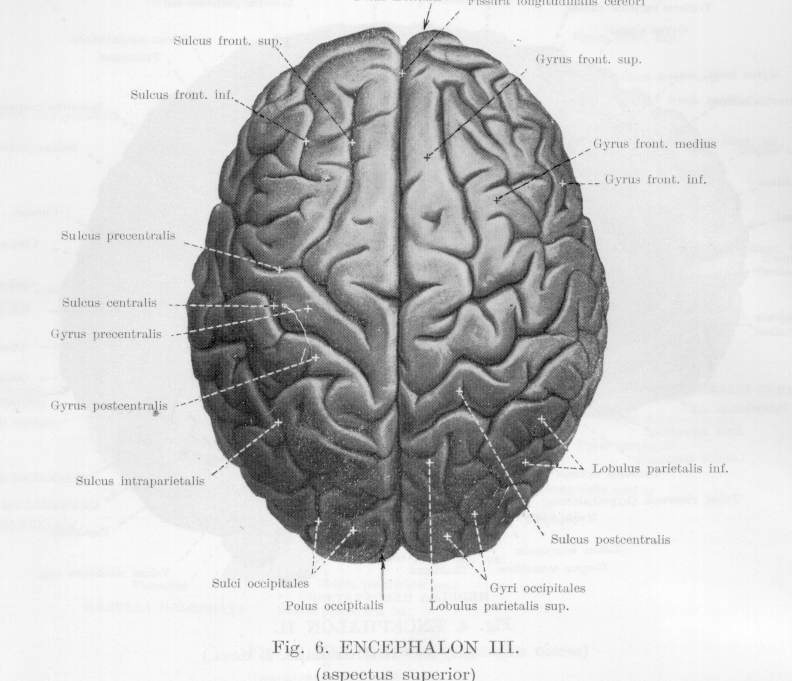

Анатомические снимки верхнелатеральной поверхности головного мозга